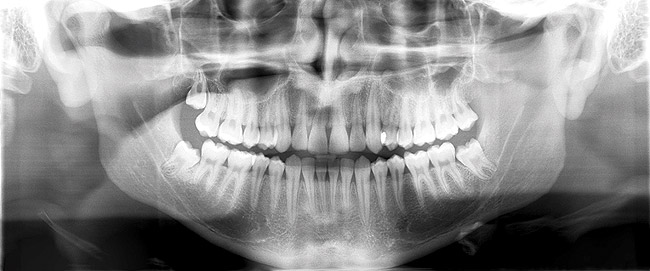

For the diagnosis of interproximal caries in posterior teeth, digital radiographic images have been shown to be equivalent to film.4 Also, for the diagnosis and evaluation of periodontal bone defects, digital images have been shown to be equivalent.5 One benefit of digital radiographs is the ability to use the software program to "process" the image (make digital adjustments to contrast, lightness and darkness, and use other tools) to better see conditions to make a more accurate diagnosis. Also, all digital radiographic programs offer a magnification tool to enlarge the image for an improved evaluation.6 Diagnosis and use of digital radiography during endodontic treatment has also become well accepted.7,8 Digital radiography through the use of digital panoramic units has improved diagnosis, and with the latest 3-D cone-beam technologies, allow for the use of extraoral imaging with excellent diagnostic potential (Figure 1).9,10 Digital radiography also provides an excellent patient education tool with the ability to use the computer monitor at chairside to better demonstrate conditions that have been diagnosed and possible proposed treatment.

Figure 1